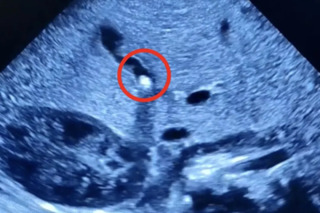

В Балаково Саратовской области у полуторамесячного мальчика в жёлчном пузыре нашли камень. Об этом сообщили в ГУЗ СО «Балаковская городская клиническая больница».

В публикации сказано, что ребёнок поступил в стационар с жалобами мамы на плохую прибавку массы тела, желтушное окрашивание кожи и склер у новорожденного. «При обследовании выяснилось, что желчный проток частично закрыт камнем небольших размеров. Находясь в стационаре, малыш получал необходимое лечение. Врачам удалось не только улучшить отток желчи из желчного пузыря, но и добиться стабильной прибавки в весе, которой не наблюдалось в первый месяц жизни ребёнка. Сейчас пациент выписан домой и находится на амбулаторном наблюдении», — говорится в официальном сообщении.